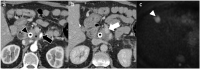

The incidence and mortality of pancreatic ductal adenocarcinoma are growing over time. The management of patients with pancreatic ductal adenocarcinoma involves a multidisciplinary team, ideally involving experts from surgery, diagnostic imaging, interventional endoscopy, medical oncology, radiation oncology, pathology, geriatric medicine, and palliative care. An adequate staging of pancreatic ductal adenocarcinoma and re-assessment of the tumor after neoadjuvant therapy allows the multidisciplinary team to choose the most appropriate treatment for the patient. This review article discusses advancement in the molecular basis of pancreatic ductal adenocarcinoma, diagnostic tools available for staging and tumor response assessment, and management of resectable or borderline resectable pancreatic cancer.